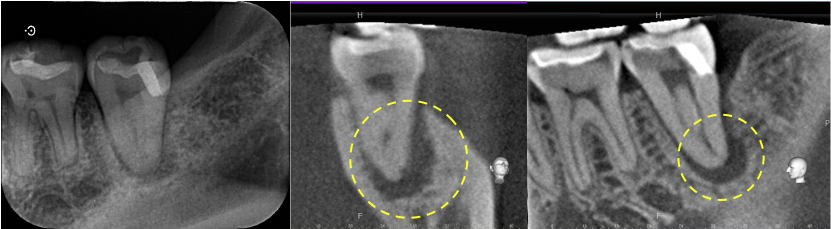

術前のレントゲン・CT画像にて、根の先に大きな黒い影が認められました。

歯の神経の状態の検査からも、神経の反応はなく、歯髄壊死(神経が死んでしまっている状態)と診断しました。